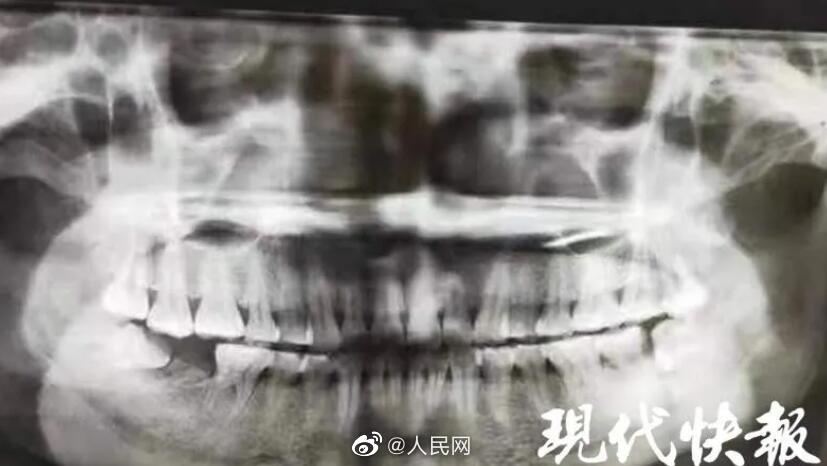

扬州。一名女子智齿反复发炎好几年,每次都靠吃消炎药硬扛,最后左侧脸颊竟被脓肿穿破。智齿前面的牙齿也被牵连,需一起拔掉。医生:该患者平时不注意口腔卫生,出现智齿冠周炎,又长期没有得到彻底治疗,导致齿槽骨破坏缺损,面颊被脓肿穿通。发生牙疼应及早就医。(现代快报)

女子智齿反复发炎,脸颊烂穿一个洞